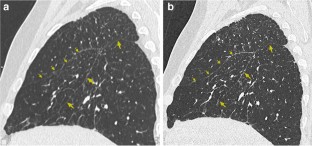

Fig. 3